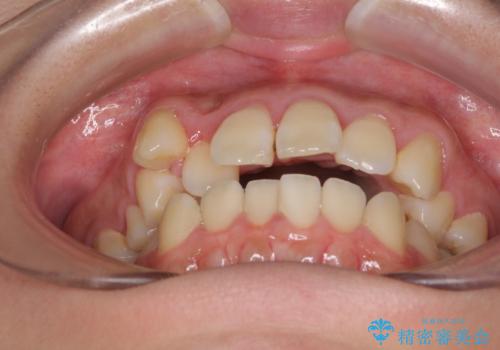

- 八重歯と叢生を気にして来院された患者様です。

上下の前歯が非接触であり、叢生や八重歯が顕著であったため、上顎左右第一小臼歯2本を抜歯して排列することとしました。

抜歯により移動量が多くなるため、ワイヤーや補助装置を活用し、その後インビザラインによる矯正治療を行うこととしました。